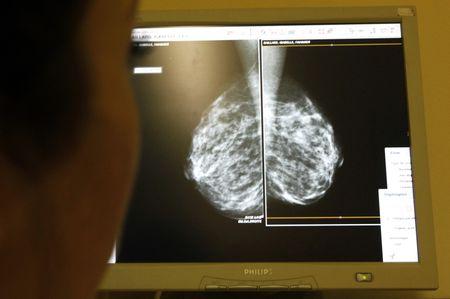

Health Rounds: Surgery may be unnecessary for common precancerous breast condition

(Reuters) – Early results from a clinical trial appear to confirm that most women with the precancerous breast condition known as ductal carcinoma in situ (DCIS) do not benefit from surgery, as researchers have long suspected.

Women with low-risk DCIS who were monitored with frequent mammograms were no more likely to progress to breast cancer over the next two years than women who had surgery to remove the abnormal cells, according to data presented on Thursday at the San Antonio Breast Cancer Symposium in Texas.

In DCIS – often called stage-zero breast cancer – abnormal cells are present inside the milk ducts, but they do not always evolve to become an invasive type of cancer.

In the U.S. alone, DCIS affects more than 50,000 women each year. Nearly all are treated with surgery, including many who undergo mastectomy.